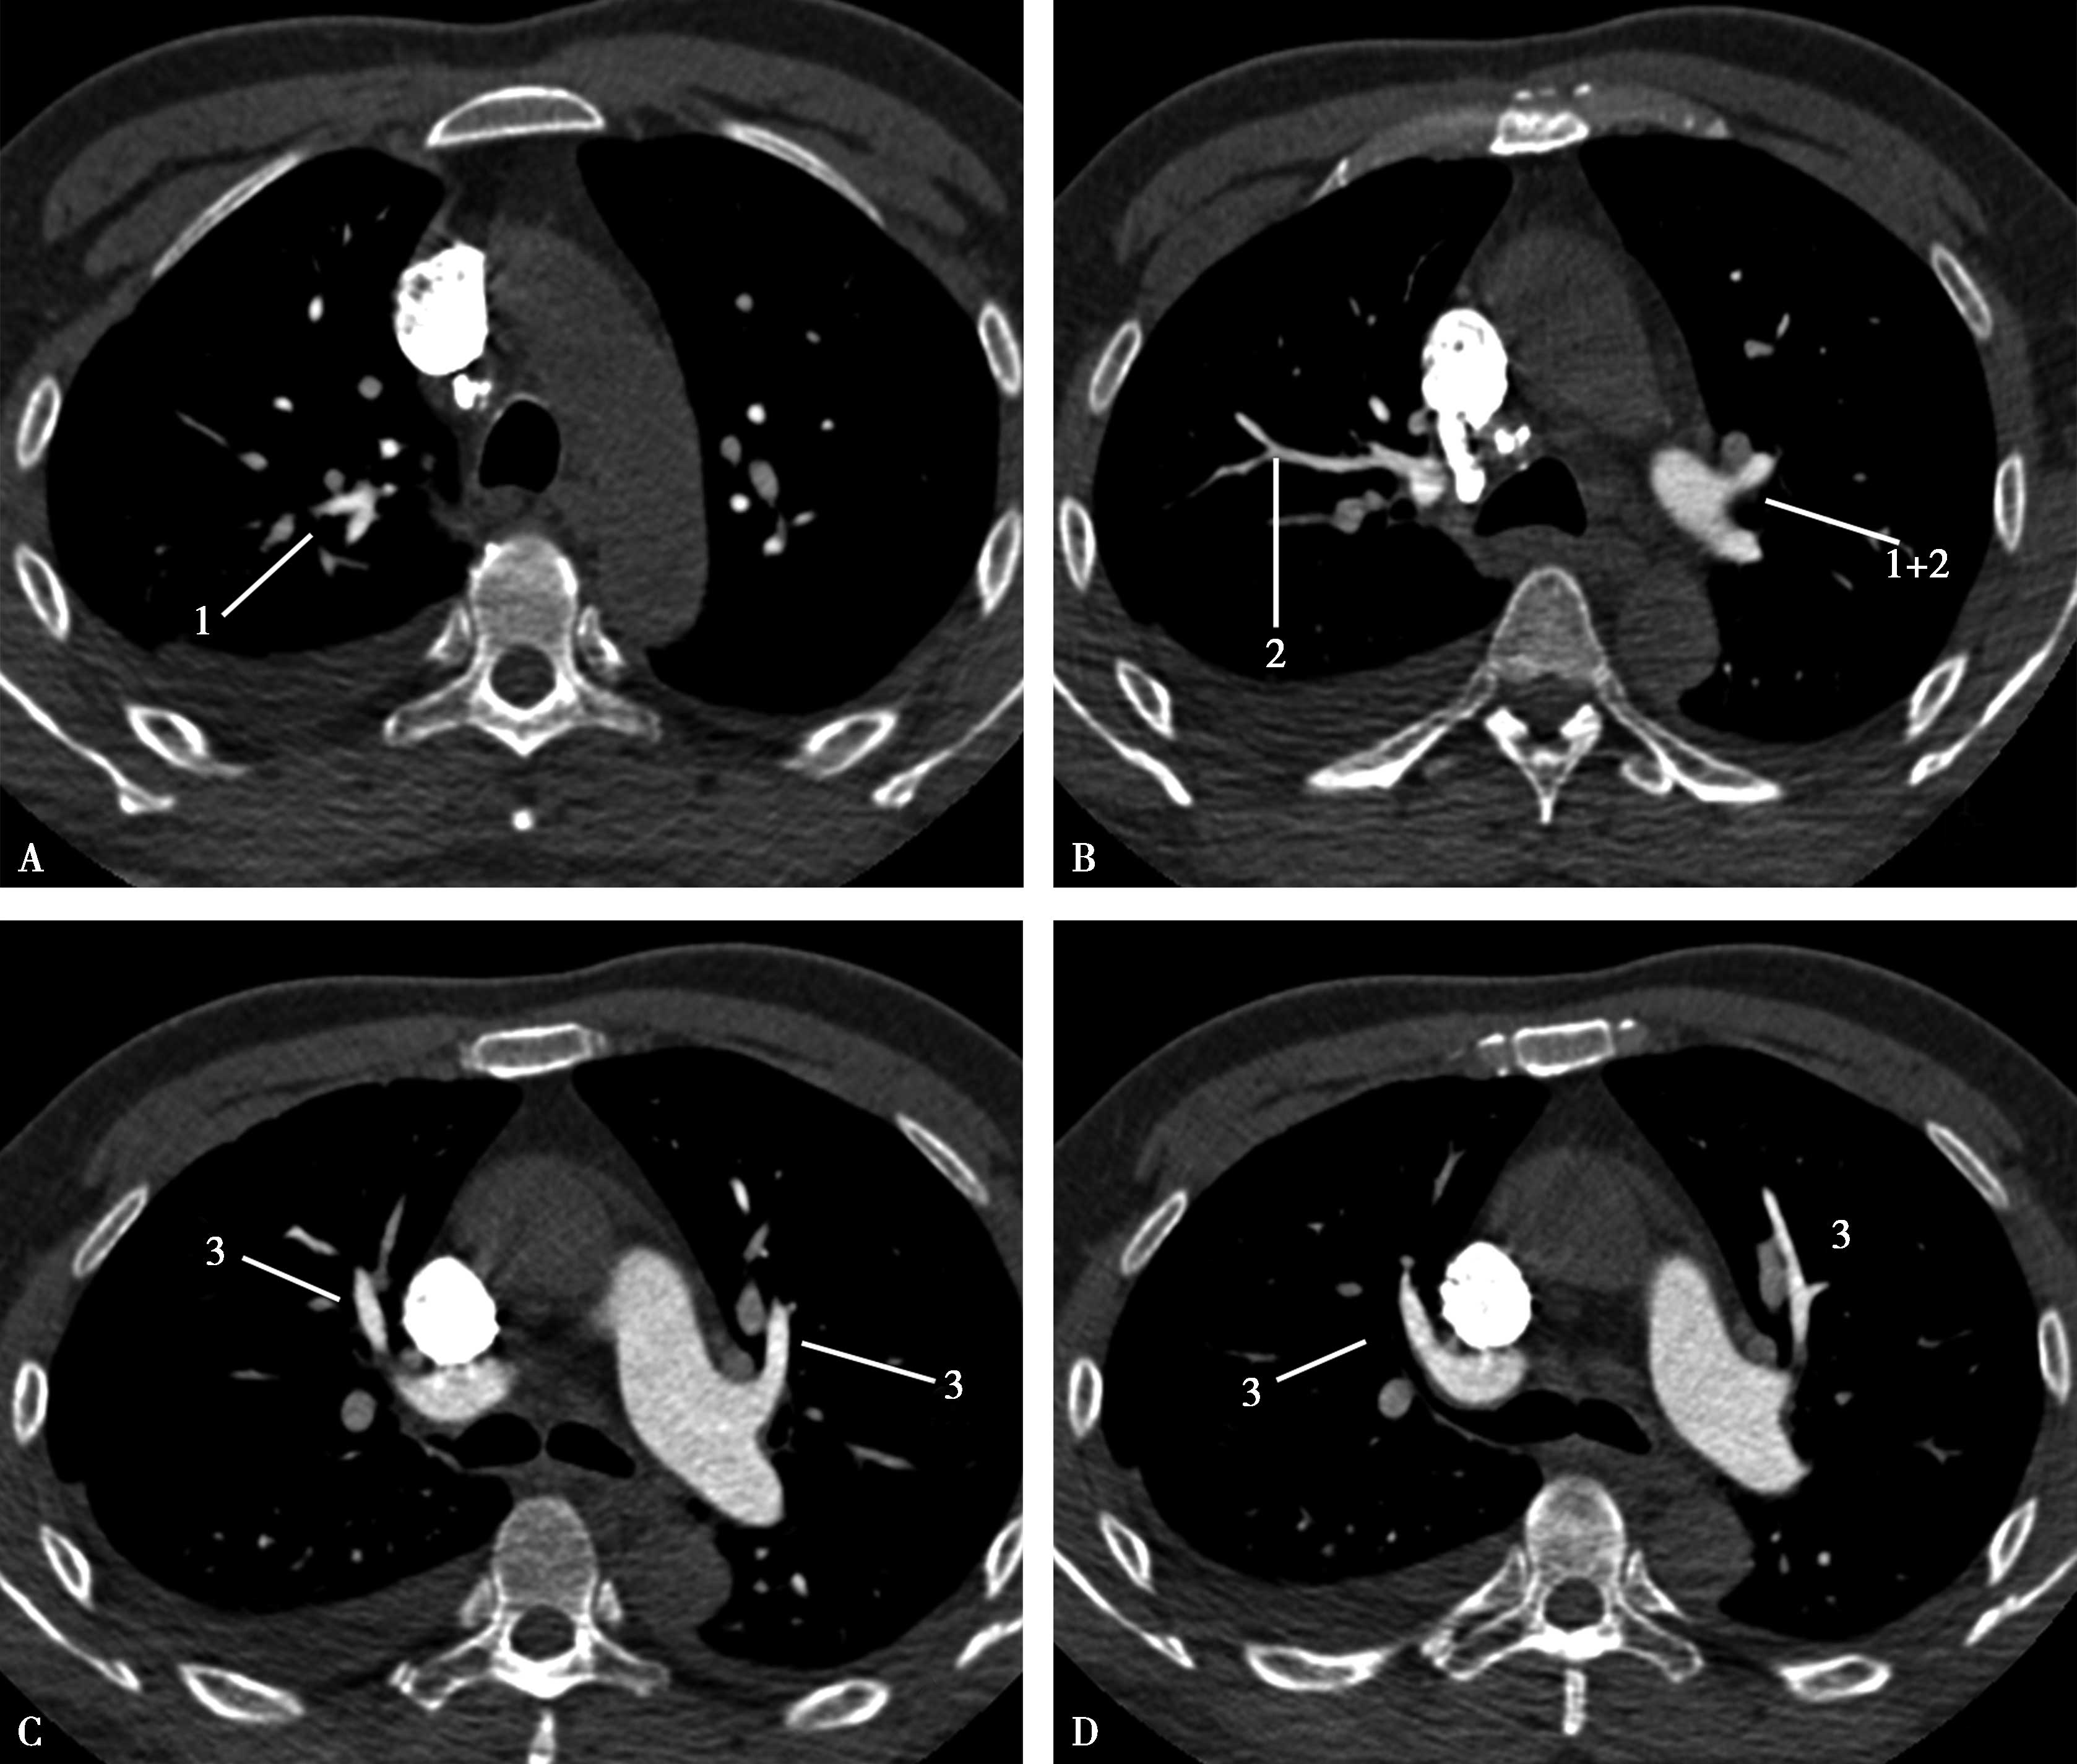

图8-2-7 肺动脉横断扫描

A~D.上叶:1.尖段;2.后段;3.前段。E~J.(右肺)中叶:4.外侧段;5.内侧段。(左肺)舌叶:4.上舌段;5.下舌段。下叶:6.背段;7.内基底段;8.前基底段;9.外基底段;10.后基底段